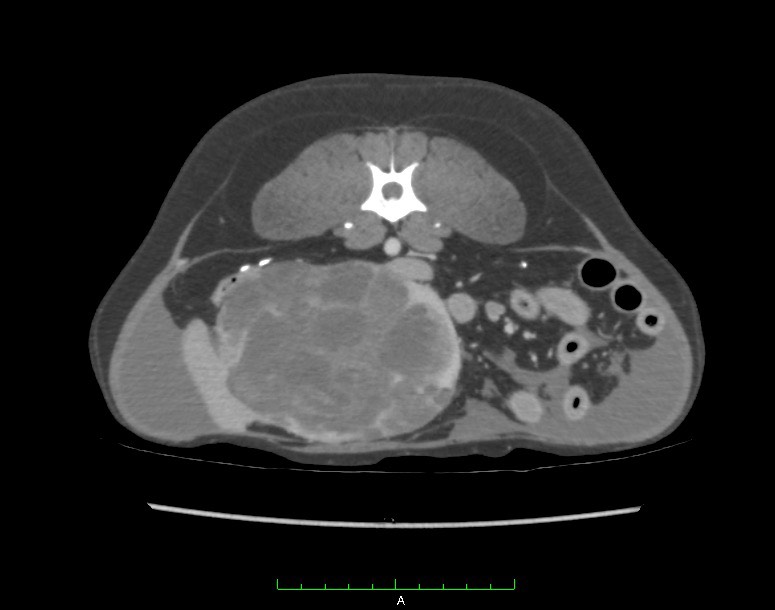

特にCT検査は悪性腫瘍の転移の有無や転移の程度を評価するのに有用です。

以下はCTの画像と手術中の画像です。

苦手な方はご注意ください。↓↓

脾臓腫瘍のCT画像